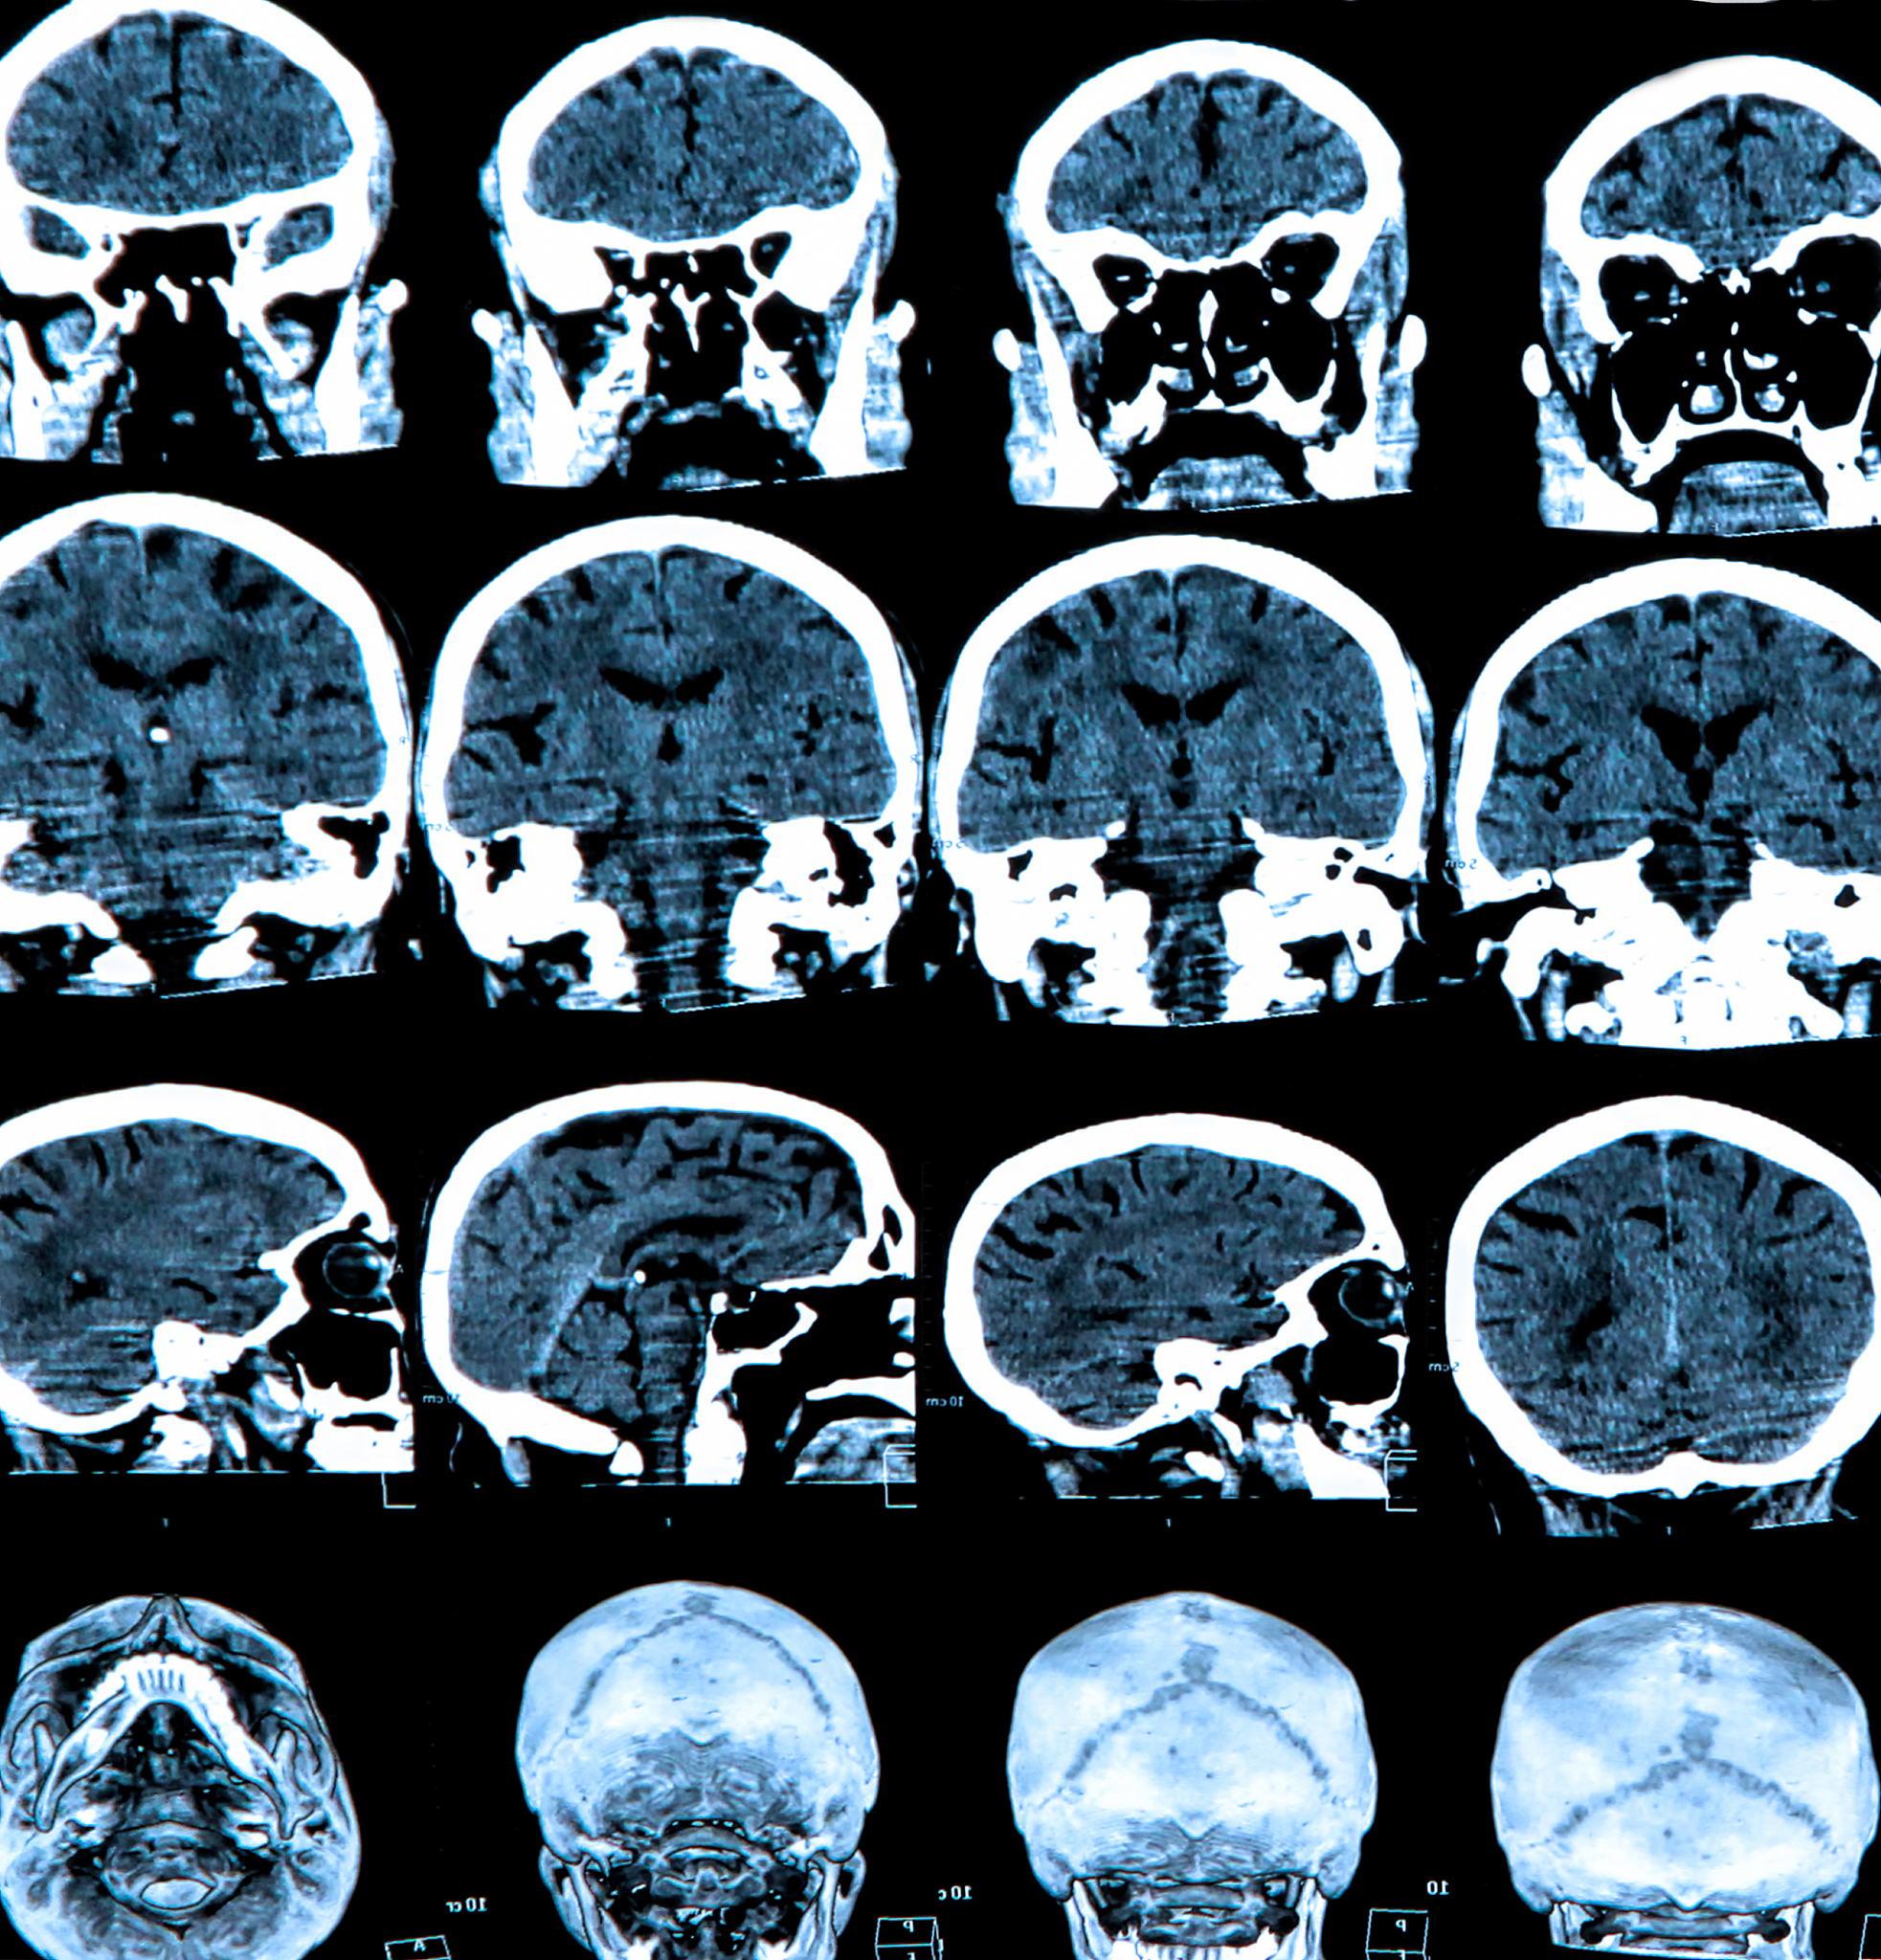

诊断闭合性颅脑损伤通常需要进行头部CT或MRI扫描来观察脑组织的损伤情况。治疗方法根据损伤的严重程度而定,可以包括休息、药物治疗、手术等。

闭合性颅脑损伤